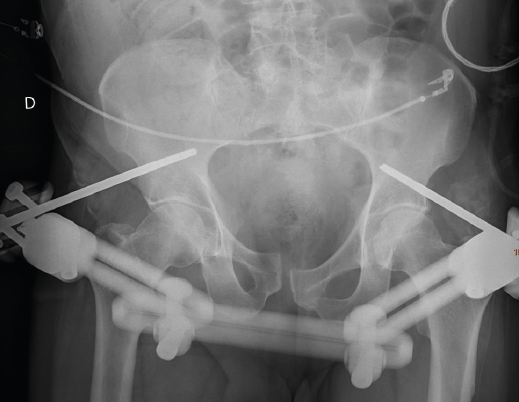

Figura 1. Radiografía de pelvis tras colocación de fijador externo con pines supraacetabulares. Puede observarse la lesión a nivel de la sínfisis púbica. Visualizar y/o caracterizar la fractura sacra en radiología convencional no es posible en un alto porcentaje de casos.

Se solicitó estudio radiológico seriado y tomografía computarizada de cuerpo (body-TC) donde se evidenciaron: fractura conminuta de ambos radios distales, fractura sacra y diástasis de la sínfisis púbica, fractura de apófisis transversas de L5 bilaterales, moderada cantidad de líquido, en probable relación con sangrado en retroperitoneo derecho sin evidencia de focos de sangrado activo, fractura esternal y focos contusivos en ambos campos pulmonares. Ante estos hallazgos, se trasladó al quirófano para realizar cirugía de control de daños, practicándose reducción cerrada y fijación externa de la fractura del radio distal derecho, reducción cerrada y colocación de yeso de la fractura del radio distal izquierdo, y reducción cerrada y fijación externa de la fractura pélvica con fijador externo Orthofix® colocando 2 pines supraacetabulares. Tras la cirugía, ingresó en la Unidad de Cuidados Intensivos (UCI) para su control evolutivo (Figura 1).